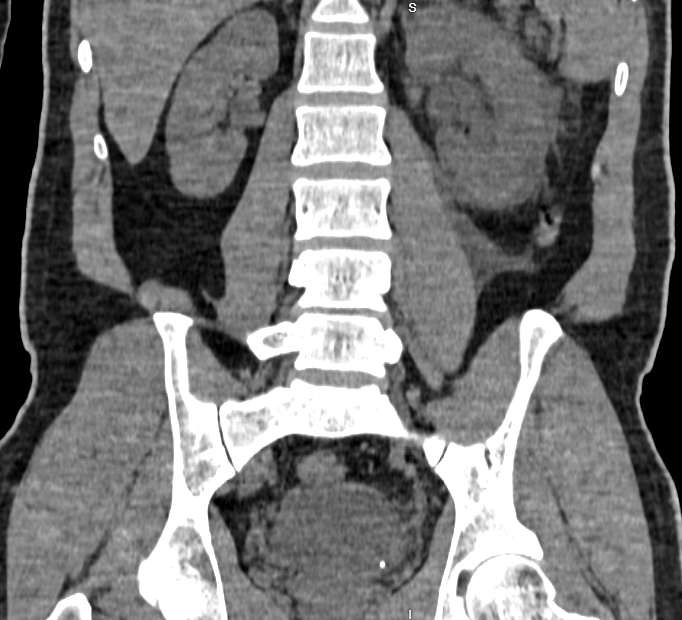

Left Kidney

- Size: Measures 11 x 4.7 cm.

- Pelvicalyceal System: Not dilated.

- Enhancement: Homogeneous enhancement during the nephrogenic phase.

- Calculus: Small calculus of size approximately 3.2 x 3 mm at the left vesico-ureteric junction, causing mild hydroureteronephrosis.

- Urothelial Thickening: Hyperenhancement involving renal pelvis and ureter, suggestive of acute pyelo-ureteritis.

- Perinephric Findings: Fat stranding, Gerota’s fascia thickening, and mild perinephric fluid collection.

- Ureter: Left ureter is not opacified on the delayed scan.

Impression

- Left Vesico-Ureteric Junction Calculus: Causing mild hydroureteronephrosis.

- Left Perinephric Fat Stranding: Gerota’s fascia thickening and mild perinephric fluid collection.

- Left Acute Pyelo-Ureteritis